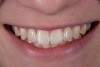

Fig 1. Initial presentation. Note midline shift to right, missing right lateral incisor, and diminutive left lateral incisor in crossbite.

Figure 1

A 14-year-old patient presented to the office with his mother (Figure 1). His chief complaint involved the large spaces between the teeth created by his missing right maxillary lateral incisor and his small left maxillary lateral incisor. He desired to replace the missing tooth with an implant and create a beautiful smile. Upon examination, he was found to have a Class I canine and molar relationship, but because he had a tooth size/arch size discrepancy and space distal to the right central incisor, the remaining incisors had drifted to the right. The left maxillary lateral incisor was peg-shaped and in a cross bite position. Studies have shown a clear association between congenitally missing teeth and reduced tooth size.59-62 Because he was only 14-years-old at the time and could not have implants placed until the cessation of growth (around 22 years old), he was sent to the orthodontist for alignment of the teeth.16,17